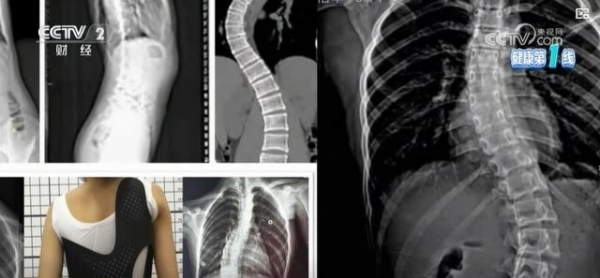

据估计,我国中小学生脊柱侧弯发生率为1%~3%,侧弯人数已超过500万,已经成为继肥胖、近视之后影响我国青少年健康的第三大危害。

除了性别因素,为什么瘦子比胖子更容易脊柱侧弯呢?严振告诉记者,"青春期突然蹿高是脊柱侧弯的危险因素。此时肌肉力量单薄,再加上平时行为体态不好,就容易导致侧弯。"

脊柱侧弯多发的原因之一,还可能与现在的孩子平时缺乏运动有关,肌肉、韧带的稳定性和平衡能力下降,脊柱没有得到很好的支撑。